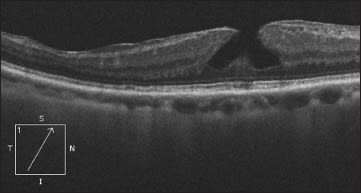

Clinical detection of a lamellar macular hole can be difficult with conventional biomicroscopic techniques. With OCT, however, they are easily diagnosed: a break in the inner fovea but intact foveal photoreceptors, intraretinal split, and irregular foveal contour but absence of a full-thickness foveal defect are characteristic findings (Figure 1)2 Lateral intraretinal splits or clefts between the inner and outer retinal layers may be seen.3

Figure 1. Lamellar macular holes are easily diagnosed with OCT: a break in the inner fovea but intact foveal photoreceptors, intraretinal split and irregular foveal contour but absence of a full-thickness foveal defect are characteristic findings.